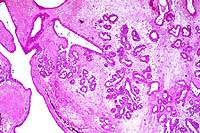

- Case 19-1. Lung. Multifocally throughout the lung,

abundant macrophages, eosinophils, neutrophils and scattered

foreign body or Langhans giant cells expand or replace alveoli

and bronchioles.

- AFIP Diagnosis: Lung: Pneumonia, granulomatous and

eosinophilic, peribronchiolar and perivascular, multifocal, moderate,

with perivascular edema, Brown Norway rat, rodent.